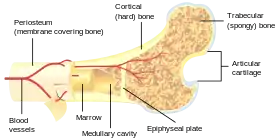

النسيج العظمي هو نسيج صلب، وهو نوع من أنواع النسيج الضام الكثيف، وله مادة خلوية تشبه قرص العسل من الداخل، تساعد على صلابة العظام. يتكون نسيج العظام من أنواع عديدة من الخلايا العظمية، تشترك الخلايا العظمية والخلايا بانية العظم في تكوين وتمعدن العظم، فيما تشارك ناقضة العظم في تشربه، بانيات العظم المعدلة تصبح الخلايا المبطنة التي تكون طبقة وقائية على سطح العظمة. تملك المادة الخلوية المتمعدنة لنسيح العظم مكون عضوي من الكولاجين بشكل رئيسي، ومكون غير عضوي من معدن العظام، يتكون من أملاح مختلفة. النسيج العظمي هو نسيج متمعدن من نوعين، عظم قشري وعظم اسفنجي. تشمل أنواع الأنسجة الأخرى الموجودة في العظم نخاع العظام، وبطانة العظم، والسمحاق، والأعصاب، والأوعية الدموية، والغضروف.

العظم ليس صلبًا بشكل موحد، وإنما يحتوي على مادة خلوية متينة. تكون تلك المادة الخلوية حوالي 30% من العظمة، فيما تتكون الـ70% الباقية من الأملاح التي تعطيها القوة. تتكون المادة الخلوية من حوالي 90-95% من ألياف الكولاجين، فيما تكون المادة الأساسية النسبة الباقية.[3] النسيج الأولي للعظمة، النسيج العظمي، يكون صلد نسبيًا وخفيف الوزن. وتتكون مادته الخلوية في الأغلب من مادة مركبة تشتمل على فوسفات الكالسيوم غير العضوي في التركيب الكيميائي المسمى هيدروكسيل أباتيت الكالسيوم (هذا هو معدن العظام الذي يعطي العظام صلابتها) والكولاجين، وهو بروتين مرن يزيد من المقاومة للكسور.[4] يعرف كولاجين العظام باسم عظمين.[5] يتكون العظم عن طريق تصلب تلك المادة الخلوية حول الخلايا المحتجزة. حين تصبح تلك الخلايا محتجزة تتحول من بانيات العظم إلى خلايا عظمية.[بحاجة لمصدر]

العظم القشري

تتكون الطبقة الخارجية الصلبة للعظام من العظم القشري الذي يسمى كذلك عظم مدمج لكونه أكثر كثافة بكثير من العظم الاسفنجي، يشكل العظم القشري القشرة الخارجية الصلبة للعظم. يعطي العظم القشري العظمة مظهرها الأبيض، الصلب، الأملس، ويمثل 80% من الكتلة العظمية الكلية في هيكل الشخص البالغ. ويسهل من الوظائف الرئيسية للعظم: دعم الجسم بالكامل، وحماية الأعضاء، وتوفير رافعات للحركة، وتخزين وإطلاق المكونات الكيميائية، بالأخص الكالسيوم. يتكون العظم القشري من العديد من الأعمدة المجهرية، يسمى كل واحد منها عظمون. كل عمود هو عبارة عن طبقات عديدة من بانيات العظم والخلايا العظمية حول قناة مركزية تسمى قناة هافرس. قنوات فولكمان توصل الأعمدة ببعض بزاوية قائمة. تلك الأعمدة نشطة أيضيًا، وكلما يحدث تشرب للعظم وتكوينه من جديد تتغير طبيعة ومواقع تلك الخلايا خلال العظمون. يغطَّى العظم القشري بسمحاق على سطحه الخارجي، وبطانة العظم على سطحه الداخلي. بطانة العظام هي الحد الفاصل بين العظم القشري والعظم الاسفنجي.[6] الوحدة التشريحية والوظيفية الأولية للعظم القشري هي العظمون.

العظم الاسفنجي

العظم الإسفنجي، يسمى كذلك العظم التربيقي،[6] هو النسيج الداخلي للعظمة الهيكلية وهو عبارة عن شبكة خلوية مسامية مفتوحة. يمتلك العظم الإسفنجي نسبة مساحة السطح للحجم أكبر من تلك في العظم القشري نظرًا لأنه أقل كثافة. يجعله هذا أضعف وأكثر مرونة. كذلك تجعله مساحة السطح الأكبر مناسبًا للنشاطات الأيضية مثل تبادل أيونات الكالسيوم. يوجد العظم الإسفنجي تقليديًا في نهايات العظام الطويلة، وبالقرب من المفاصل، وفي داخل الفقرات. العظم الإسفنجي وعائي بشكل كبير ويحتوي عادة على نخاع عظام أحمر حيث يتم تكوين الدم، أي إنتاج خلايا الدم. الوحدة التشريحية والوظيفية الأولية للعظم الإسفنجي هي التربيق. تصطف الترابيق نحو توزيع الحمل الميكانيكي الذي يواجه العظام في العظام الطويلة مثل عظم الفخذ. فيما يخص العظام القصيرة، تم دراسة توزيع الترابيق في الفقرات.[7] تصنع تشكيلات رفيعة من بانيات العظم المغطاة ببطانة العظم شبكة غير منتظمة من المساحات،[6] تعرف باسم الترابيق. خلال هذه المساحات يوجد نخاع العظام والخلايا الجذعية المكونة للدم التي تكون الصفائح الدموية، وكريات الدم الحمراء، وخلايا الدم البيضاء.[6] النخاع التربيقي يتكون من شبكة العناصر المشابهة للعصيان ووالصفائح تجعل العضو أخف وتوفر مساحة للأوعية الدموية ونخاع العظام. يمثل العظم الإسفنجي 20% من الكتلة العظمية الكلية لكن مساحة سطحه تبلغ تقريبًا 10 أضعاف العظم القشري.[8]